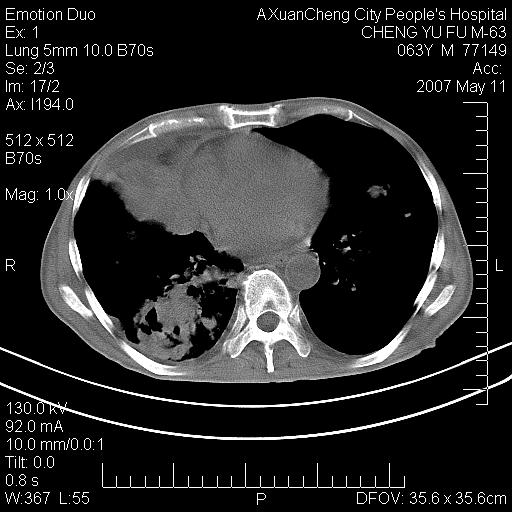

以下是引用小初学者在2007-5-11 19:32:00的发言:[br]1、首先考虑干酪性肺炎支气管播散[br]2、支气管肺泡癌待排

以下是引用zhangzhongshou在2007-5-11 19:30:00的发言:[br]细支气管肺泡癌可能性大。